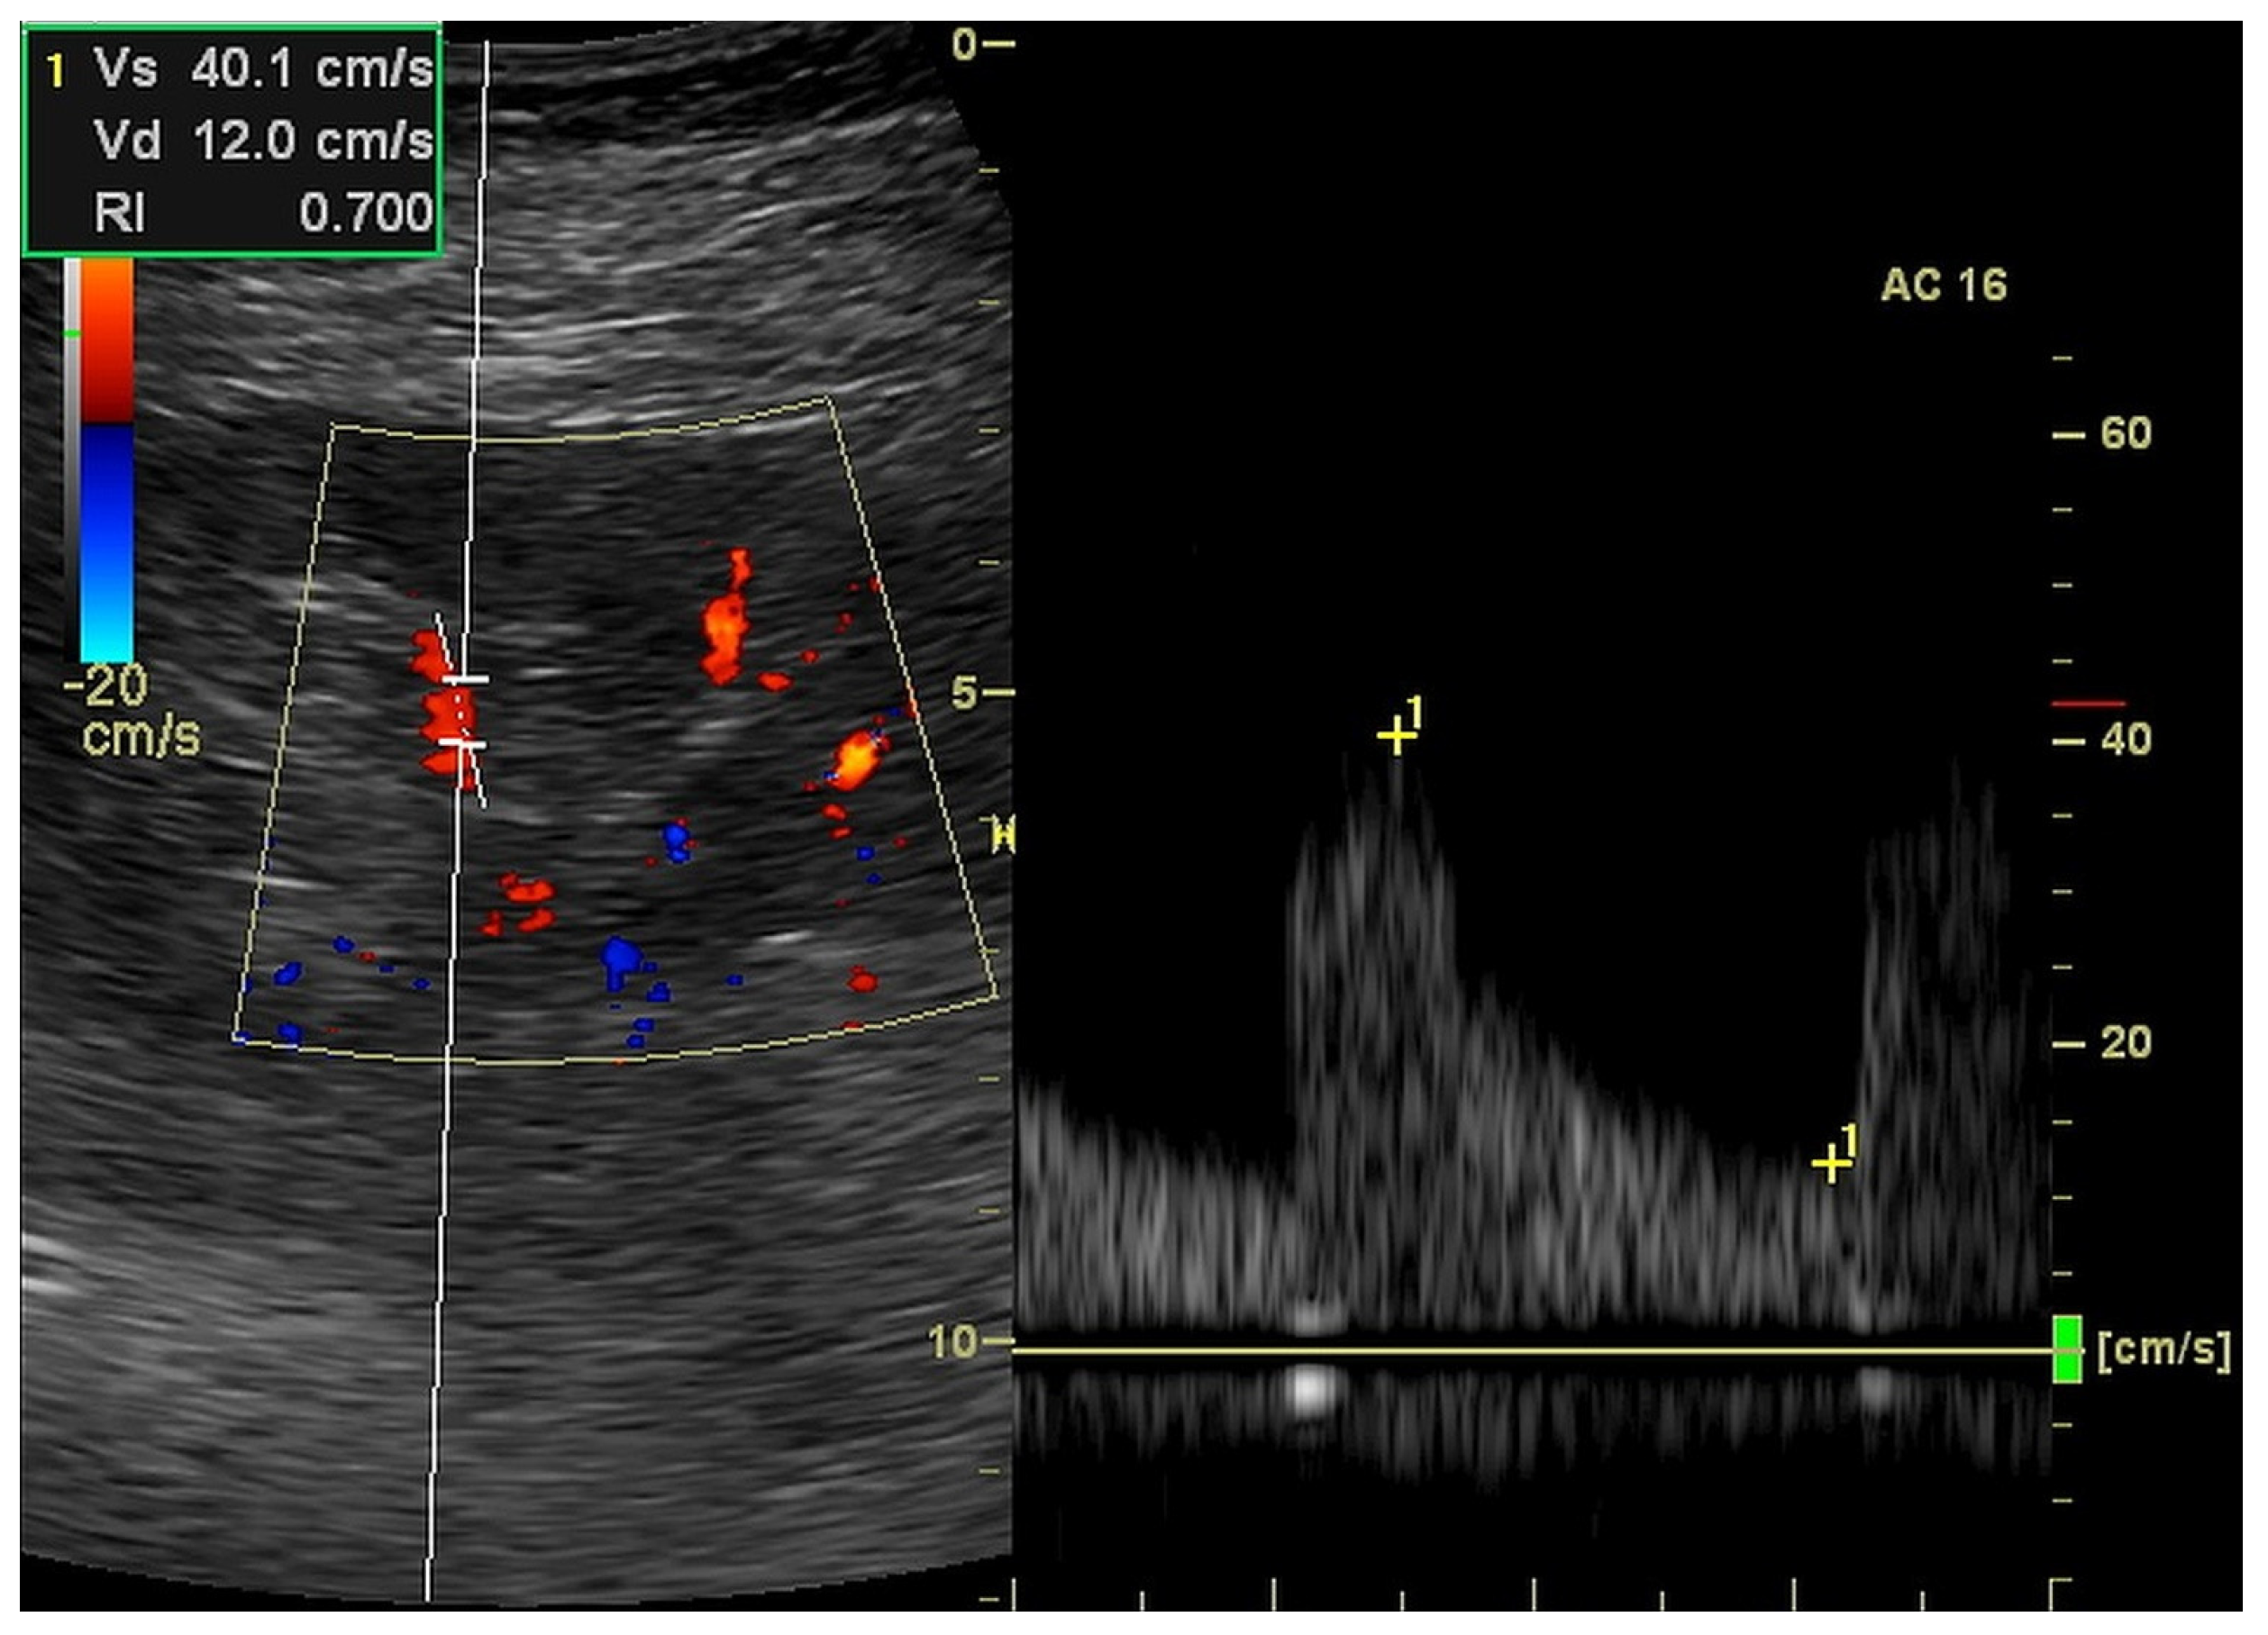

| RI (ratio) | 0.701 | 0.115 | 0.721 | 0.169 |

| EDV (cm/s) | 13.6 | 5.6 | 12.2 | 9.7 |

| dRI (ratio) | 0.735 | 0.168 | 0.760 | 0.205 |

| dPI (ratio) | 1.433 | 0.582 | 1.430 | 0.930 |

| dRCP (cm/s) | 0.483 | 0.452 | 0.303 | 0.529 |